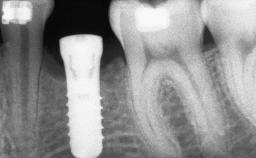

Iliac and Calvarial Bone Blocks for Onlay Grafting of a Severely Resorbed Edentulous Maxilla

# of Implants 8

Type of Implants Reduced-Diameter|Two-Piece

Bone Augmentation Horizontal|Sinus Floor Elevation|Staged|Vertical

Augmentation Materials Autogenous chips|Autogenous block(s)